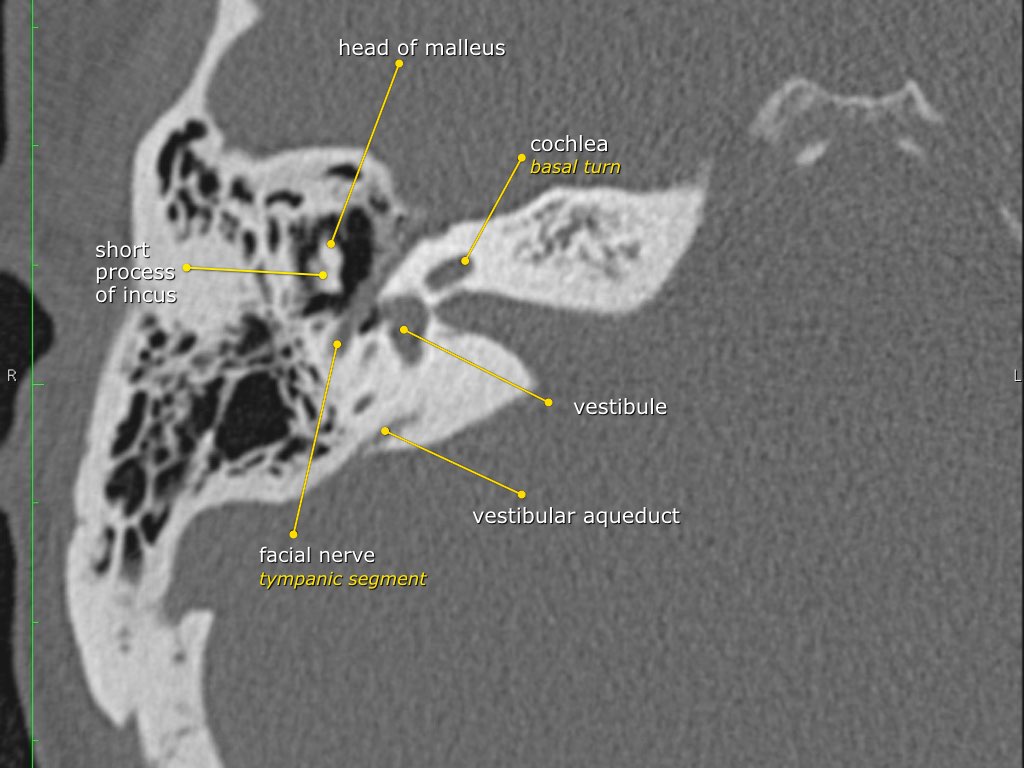

Trong bài tổng quan này, chúng tôi trình bày giải phẫu bình thường trên mặt phẳng cắt ngang (axial) và mặt phẳng cắt đứng ngang (coronal) của xương thái dương thông qua việc duyệt qua các hình ảnh.

Một số cấu trúc được thảo luận chi tiết hơn với trọng tâm là các bệnh lý liên quan.

Giải phẫu xương đá trên mặt phẳng cắt ngang (Axial)

Nhấp vào hình ảnh để phóng to.

Cuộn qua các hình ảnh.

Dây thần kinh mặt

Đoạn mê nhĩ của dây thần kinh mặt xuất phát từ ống tai trong, chạy gần như vuông góc với trục dài của xương đá, gập góc nhọn về phía trước để đến hạch gối (geniculate ganglion).

Tại hạch gối, dây thần kinh mặt tạo thành một khúc quặt hình chữ U (genu thứ nhất của dây thần kinh mặt) để chạy ra phía sau theo đoạn nhĩ dọc theo thành trong của thượng nhĩ.